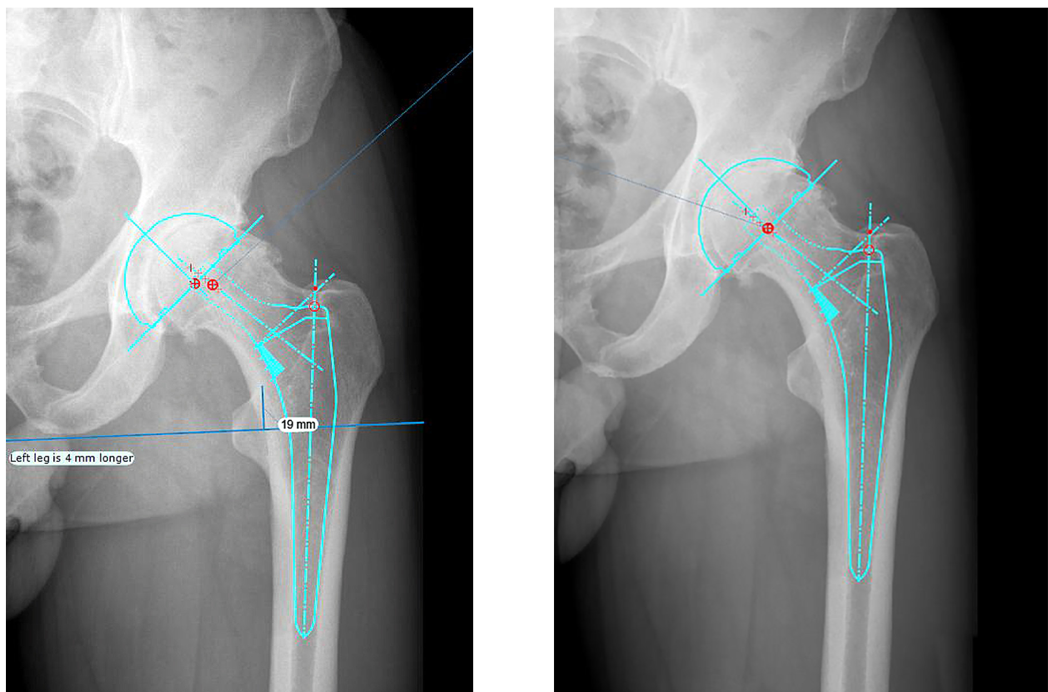

A 76-year-old man underwent right total hip arthroplasty. He fell from a step ladder and is unable to bear weight on his right side. A radiographic evaluation reveals a Vancouver B2 periprosthetic femur fracture. What is the best next step?